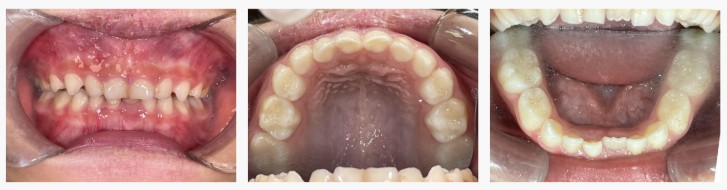

▼ Before(治療前)

初診時の診察では、

・あごの大きさに対して永久歯が生えるスペースが不足

・将来的にガタガタが強くなる可能性

が認められ、典型的な 叢生(歯の重なり・乱れ) の兆候がありました。